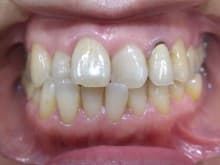

口臭と歯周病

こんにちは! 歯科衛生士の山崎です。 本日も歯周専門治療のご紹介をしていきたいと思います。 治療前 治療前、ご本人に歯周病の自覚がありませんでしたので、実際の口腔内写真と…